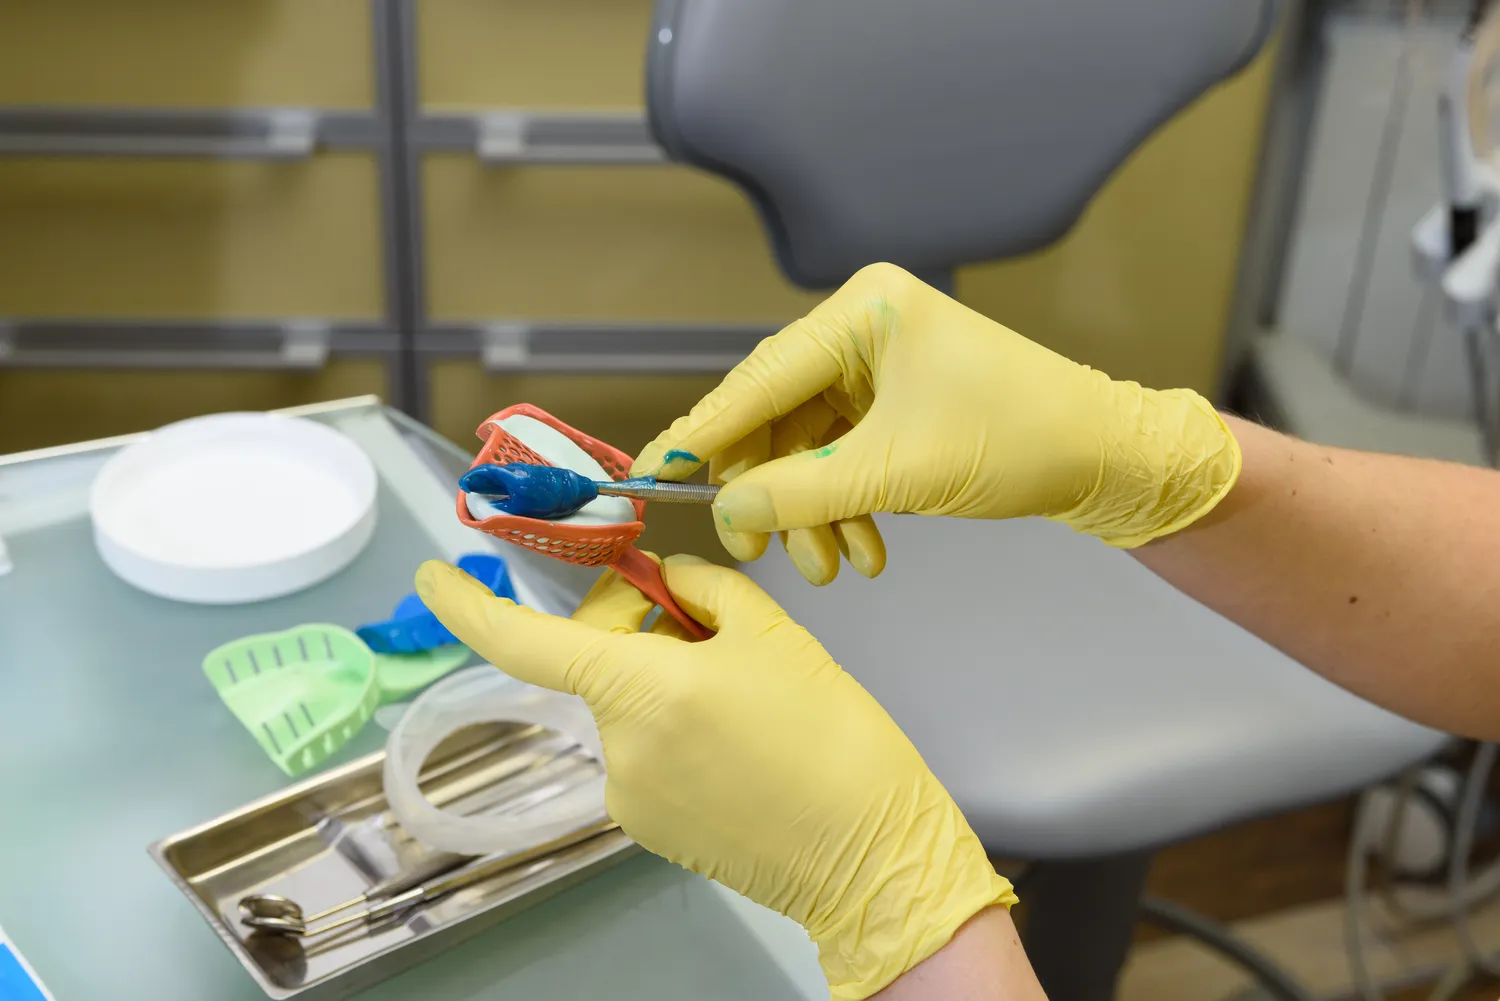

Proces leczenia protetycznego w Szczecinie zazwyczaj rozpoczyna się od dokładnej diagnostyki jamy ustnej pacjenta. Stomatolog przeprowadza szczegółowe badanie oraz wykonuje zdjęcia rentgenowskie, aby ocenić stan uzębienia oraz kości szczęki. Na podstawie tych informacji lekarz może zaproponować odpowiednie rozwiązania protetyczne dostosowane do indywidualnych potrzeb pacjenta. Kolejnym krokiem jest opracowanie planu leczenia, który może obejmować różne etapy – od przygotowania zębów do założenia koron czy mostów po wykonanie protez ruchomych lub wszczepienie implantów. W przypadku implantów konieczne jest także przeprowadzenie zabiegu chirurgicznego, który polega na wszczepieniu implantu w kość szczęki. Po zakończeniu tego etapu następuje czas gojenia, który może trwać kilka miesięcy. Po zagojeniu się tkanek stomatolog przystępuje do wykonania ostatecznych uzupełnień protetycznych, takich jak korony czy mosty.

Nowoczesne technologie w protetyce zębów w Szczecinie znacząco poprawiają jakość usług oraz komfort pacjentów. Wiele gabinetów stomatologicznych korzysta z zaawansowanych technologii, takich jak skanery wewnątrzustne, które umożliwiają dokładne odwzorowanie kształtu jamy ustnej pacjenta bez konieczności stosowania tradycyjnych odcisków. Dzięki temu proces tworzenia protez jest szybszy i bardziej precyzyjny, co przekłada się na lepsze dopasowanie uzupełnień. Kolejnym innowacyjnym rozwiązaniem są drukarki 3D, które pozwalają na szybkie i dokładne wykonanie modeli oraz protez dentystycznych. Technologia ta umożliwia także personalizację uzupełnień, co sprawia, że są one bardziej estetyczne i funkcjonalne. Warto również wspomnieć o cyfrowym projektowaniu uśmiechu, które pozwala pacjentom zobaczyć, jak będą wyglądały ich zęby po leczeniu protetycznym jeszcze przed rozpoczęciem zabiegów. Takie podejście zwiększa komfort psychiczny pacjentów oraz pozwala na lepsze dostosowanie planu leczenia do ich oczekiwań.